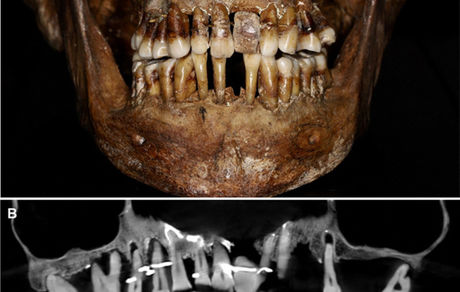

دانشمندان راز دیرینه یک بانوی اشرافی فرانسوی قرن هفدهم را چهارصد سال پس از مرگش کشف کردند: او با استفاده از سیم طلا،…